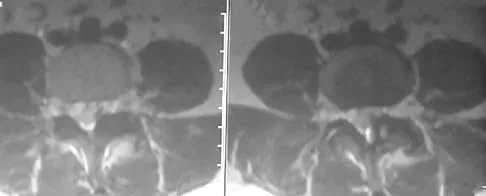

A patient has right shoulder pain. Figure 1a shows a gadolinium-enhanced transverse MRI scan at the level of the coracoid. Figure 1b shows an arthroscopic view of the anterior structures from a posterior portal. These images reveal which of the following findings?

The area shown in the arthroscopic view and MRI scan is referred to as a Buford complex and represents a normal labral variant. It consists of a thickened, cord-like middle glenohumeral ligament, a superior labral attachment of the middle glenohumeral ligament just anterior to the biceps tendon, and absence of the anterosuperior labrum. This combination of findings can be confusing and may simulate labral pathology. Mistaken repair of the lesion back to the glenoid rim can result in significant loss of external rotation. A Bankart lesion would be located at the inferior anterior glenoid rim. The subscapularis is seen anterior to the labrum. Normal variations that occur in the anterosuperior labrum can simulate pathology. Gusmer PB, Potter HG, Schatz JA, et al: Labral injuries: Accuracy of detection with unenhanced MR imaging of the shoulder. Radiology 1996;200:519-524. Griffin LY (ed): Orthopaedic Knowledge Update: Sports Medicine. Rosemont, IL, American Academy of Orthopaedic Surgeons, 1994, pp 47-63.

- Williams MM, Snyder SJ, Buford D Jr: The Buford complex: The "cord-like" middle glenohumeral ligament and absent anterosuperior labrum complex. A normal anatomic capsulolabral variant. Arthroscopy 1994;10:241-247.